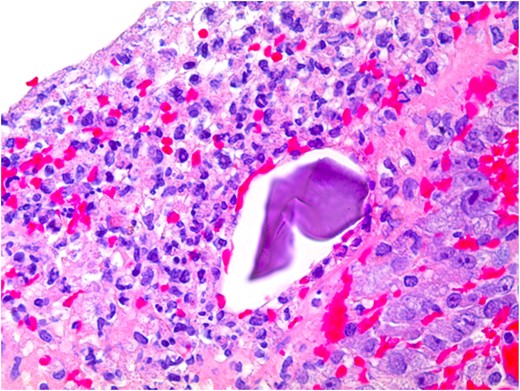

At pathological examination, the mucosa was diffusely hemorrhagic with extensive multifocal ulcerations. Crystalloid particles consistent with Kayexalate were identified throughout the bowel wall (Figs 1 and 2). There was no evidence of neoplasia or viral inclusions and cytomegalovirus immunostains were negative. Thus, a diagnosis of kayexalate-induced colon ischemia and necrosis was made.

Kayexalate crystal within colonic mucosa and surrounding necrosis.

The presence of kayexalate crystals on pathology specimens distinguishes kayexalate-induced necrosis from ischemic necrosis. Otherwise, these entities have a similar presentation. Identification of rhomboid or triangular, basophilic crystals with a mosaic pattern on hematoxylin and eosin (H & E) stain is pathognomonic for the presence of kayexalate (Figs 1 and 2). These crystals are identified adherent to the mucosa or imbedded within inflammatory milieu and ulceration [10].